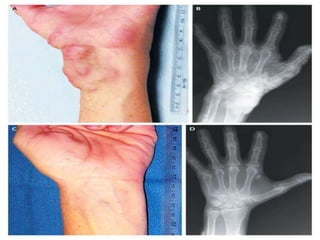

Trousseau sign:

(very uncomfortable and painful)

   A blood pressure cuff is

inflated to a pressure

above the patients

systolic level.

   Pressure is continued for

several minutes.

   Carpopedal spasm:

* flexion at the wrist

* flexion at the MP joints

* extension of the IP joints

* adduction

thumbs/fingers

Trousseau sign: (very uncomfortable and painful)  A blood pressure cuff is inflated to a pressure above the patients systolic level.  Pressure is continued for several minutes.  Carpopedal spasm: * flexion at the wrist * flexion at the MP joints * extension of the IP joints * adduction thumbs/fingers